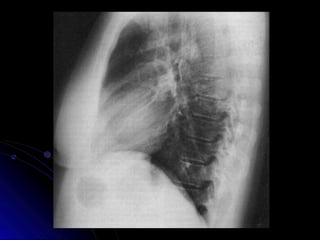

Toracica Lateral

Estructuras

Visualizadas

•Cuerpos Vertebrales

•Espacios Discales

•Escapula

•Costillas

•Diafragma

•Hila Pulmonar

Dimension de la Jaula Toracica

● En una proyección de tórax lateral se mide la

distancia desde el esternón posterior a la

superficie anterior del cuerpo vertebral de la

octava toracica. Distancia minima en

hombres es de 11 mm, con 9 mm en

mujeres.

● Indicativo de sindrome de espalda recta,

posible complicaciones cardiacas.